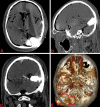

Background and Objectives Few simulation models are available that provide neurosurgical trainees with the challenge of distorted skull base anatomy despite increasing importance in the acquisition of safe microsurgical and endoscopic techniques. We have previously reported a unique training model for skull base neurosurgery where a polymer is injected into a cadaveric head where it solidifies to mimic a skull base tumor for resection. This model, however, required injection of the polymer under direct surgical vision via a complicated alternative approach to that being studied, prohibiting its uptake in many neurosurgical laboratories. Conclusion We report our updated skull base tumor model that is contrast-enhanced and may be easily and reliably injected under fluoroscopic guidance. We have identified a map of burr holes and injection corridors available to place tumor at various intracranial sites. Additionally, the updated tumor model allows for the creation of mass effect, and we detail the variation of polymer preparation to mimic different tumor properties. These advancements will increase the practicality of the tumor model and ideally influence neurosurgical standards of training.